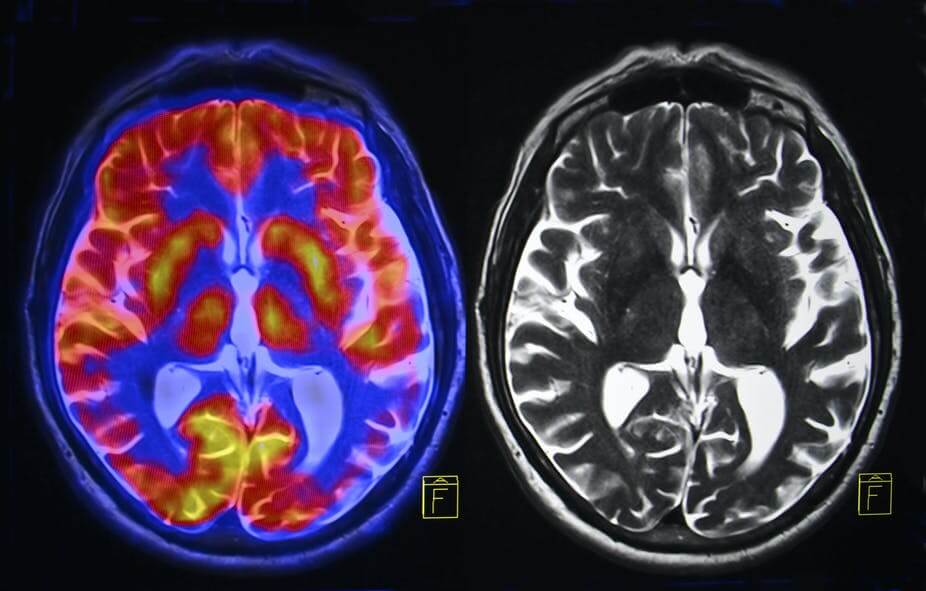

Что происходит с мозгом при смерти близкого человека?

. , , . 2019 , Social Cognitive and Affective Neuroscience, , . : .